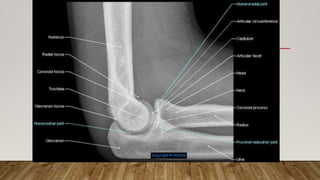

This document discusses radiology and the use of x-rays. It begins with an introduction to radiology and x-rays, noting their importance as the "father of medical investigations." It then discusses anatomy as seen on radiographs and whether x-rays are enough. The document goes on to compare gross views to radiological views, noting what each can and cannot show. It highlights important figures in the development of radiology, from x-rays to CT, MRI, and ultrasound. Specific anatomical structures visible on upper and lower limb x-rays are listed. The document concludes by discussing how pathologies appear on x-rays and the importance of clinical history and knowledge when interpreting radiological images.